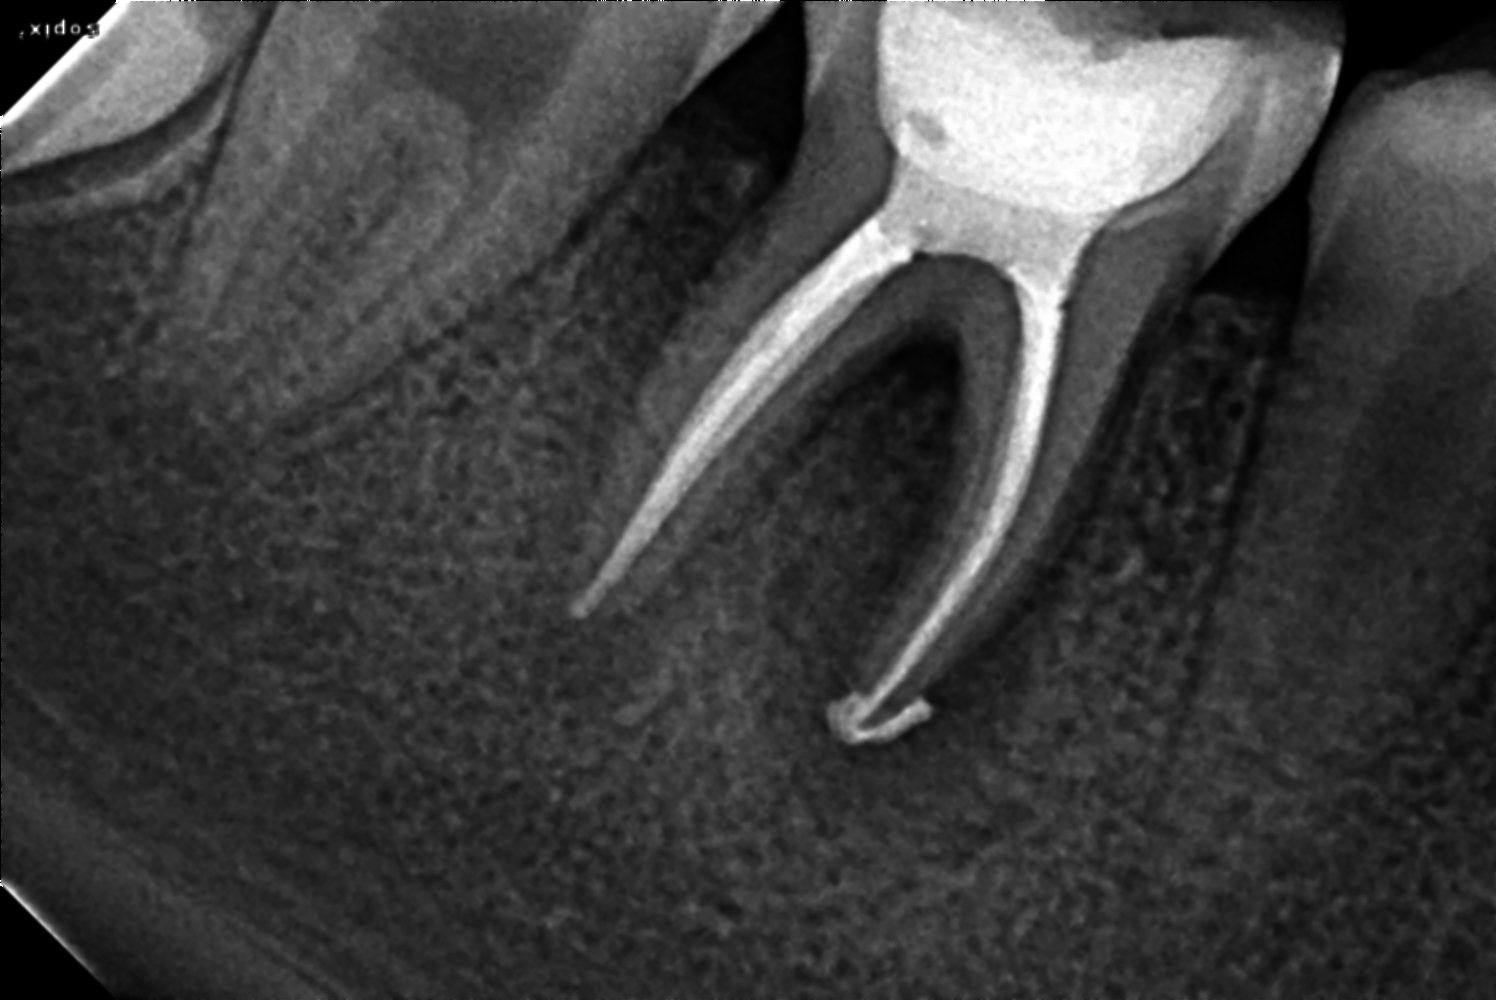

Treatmentsobturation done

bioceramic sealer

composite filling

77

Date of visit18/11/2021

C/C & Rx plansnon vital

Treatmentsacess opened 46

MB 17.5 ML 17 (4 % 25)

DB 17 DL 18.5 (6 % 25)